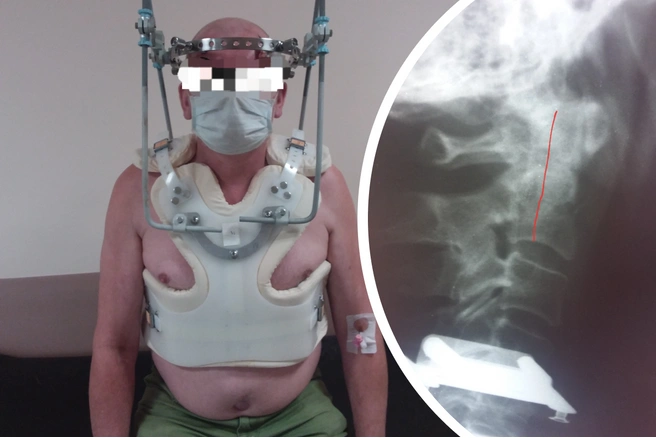

Чтобы поставить позвонок на место, пришлось использовать специальную систему гало-фиксации: на тело установили корсет, к черепу присоединили кольцо, через корсет на туловище обеспечивается тяга, за счет которой постепенно выправляется смещенный позвонок и стабилизируется.

— Этапно мы оттрепанировали этот перелом. Пациент выписан в удовлетворительном состоянии. Но с такой конструкцией ему предстоит ходить до 2 месяцев, — отмечает заведующий отделением Константин Тутынин.